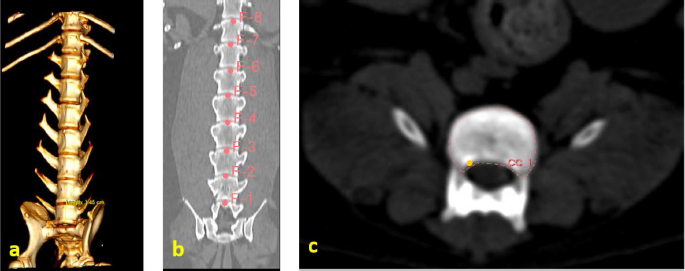

A necropsy was performed on the animal, during which the lumbar vertebrae from L1 to L7 were separated (Fig. 1a–c). The resulting segment was frozen in a refrigerator at −20°C. The segment obtained in the biomechanical study was gradually thawed to room temperature (22°C). The segment was treated, and the surrounding muscular and fatty connective tissues were separated. Each vertebra was separated, and the spinal cord was removed.

Fig. 1. (a) Canine lumbar caudo-cranial vertebrae view. (b) Canine lumbar latero-lateral vertebrae view. (c) Canine lumbar dorsoventral vertebrae view.

Evaluating errors

Two types of data were used for determining the vertebrae pressure–stretch relationships. The first was vertebra geometry data, which were retrieved directly from CT images of the euthanized dog. The CT images were imported into 3D Slicer v4.13 (Fedorov et al., 2012), ITK-SNAP (Yushkevich et al., 2006) and Osirix Lite (Rosset and Spadola, 2004) for further analysis. To estimate the confidence interval, we used three different software: 3D Slicer, Osirix Lite, and ITK-SNAP. The second type of data was that obtained from the compression machine MultiTest 2.5-i, which were presented as force (measured in N) and displacement (measured in mm). Therefore, we needed geometric data of the vertebrae to evaluate the stress–strain relationships. At first, the lengths of the vertebrae were measured by dropping two markup fiducial points and obtaining the distance between them by switching to the Markups module in 3D Slicer, selecting both fiducial points in the list, and right-clicking in the list. The fiducial points were marked between longitudinal axes of the vertebrae; one assumes the compressions are placed on the rostrocaudal axis of the vertebrae. Later, the surface area of the loading vertebra contact zone was determined by marking the intervertebral zone with a closed curve (CC) and obtaining the surface area of the close curve in the same Markups module of 3D Slicer. The obtained results are presented in Tables 1 and 2. In addition, the confidence intervals of the measured vertebrae lengths and loading surfaces were evaluated using the following expression (King and Eckersley, 2019):